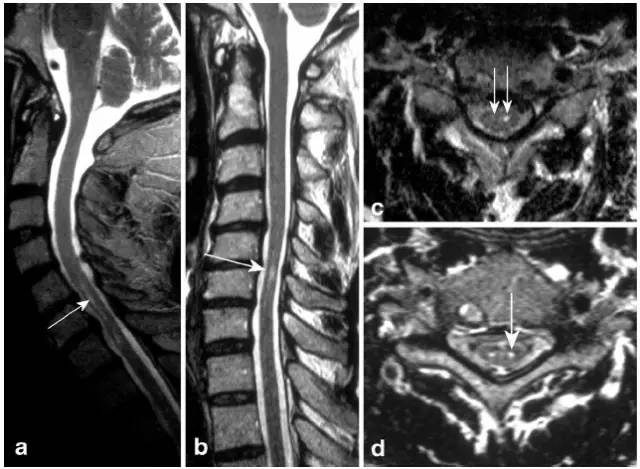

病例7:71岁男性,腹部外科手术后在ICU发生顽固低血压,导致脊髓前动脉分布区血流动力学性梗死。矢状位T2显示铅笔画样高信号(图a,箭头),轴位T2(图b-d)显示蛇眼征

病例8:腰膨大和脊髓圆锥梗死。T2(图a矢状位,图d和e轴位)显示脊髓圆锥近完全横贯性高信号,T1可见轻微强化(图c)